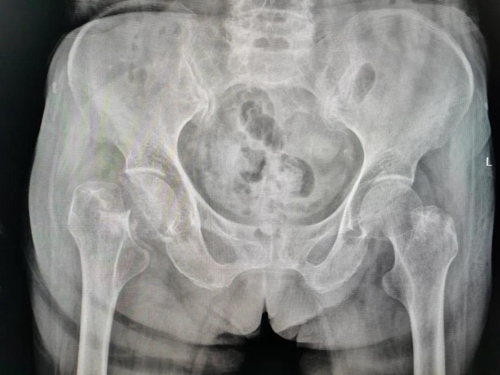

上個月,百歲的矯奶奶在家不慎摔倒,臥床在家休養(yǎng)幾天后仍疼痛難忍,子女們迅速將其送到青島婦兒醫(yī)院城陽院區(qū),矯奶奶被診斷為“右股骨頸骨折”。

本著“創(chuàng)傷小、出血少、時間短”的原則,在麻醉科的保駕護航下,骨科藍主任團隊為矯奶奶順利實施了“人工股骨頭置換術”。不到一小時即完成了假體的安裝和調試,術中出血量不足100毫升。術后拍片顯示手術非常成功,假體位置良好。